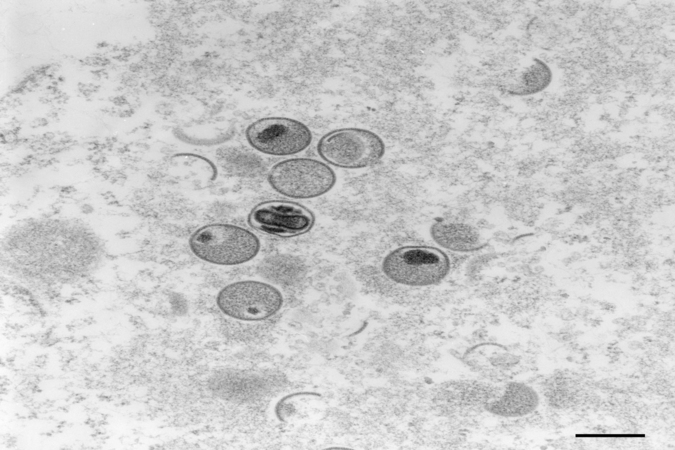

Detectada pela primeira vez em humanos em 1970, a varíola do macaco é menos perigosa e contagiosa do que a varíola, que foi erradicada em 1980.